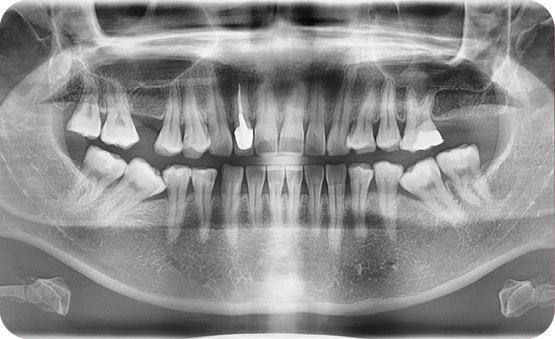

미니스크류를 이용한 돌출입 비 발치 교정

Before

After